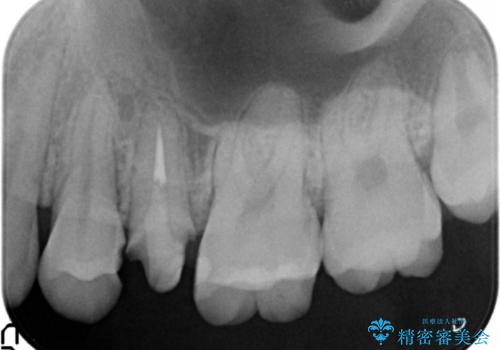

精査したところ、左上の小臼歯(左上5)は被せ物がないまま放置していたことにより、両隣の歯が寄ってきてスペースが少なくなり、また隣の歯(左上4)も虫歯になっていました。

隣の歯の虫歯治療(保険内のレジン充填)後、セラミッククラウンによる補綴を行いました。

以前つけた被せ物は1週間でとれてしまったそうで、歯ぎしりのご自覚もあることから、咬み合わせの調整を丁寧に行いました。

仮歯およびクラウンの仮付け期間を設け、はずれにくいことや咬み合わせに問題がないことを確認した上で本付けを行いました。

- かみ合わせや歯ぎしりが強すぎる方はセラミックが割れてしまう可能性があります